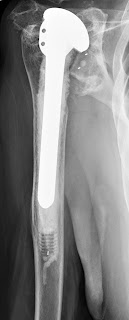

The x-rays below show a few of the many cases referred to us because of failure of a shoulder arthroplasty. You will note a very common theme: humeral components placed too high with associated glenoid problems.

High cemented stem with cuff deficiency superior humeral head subluxation